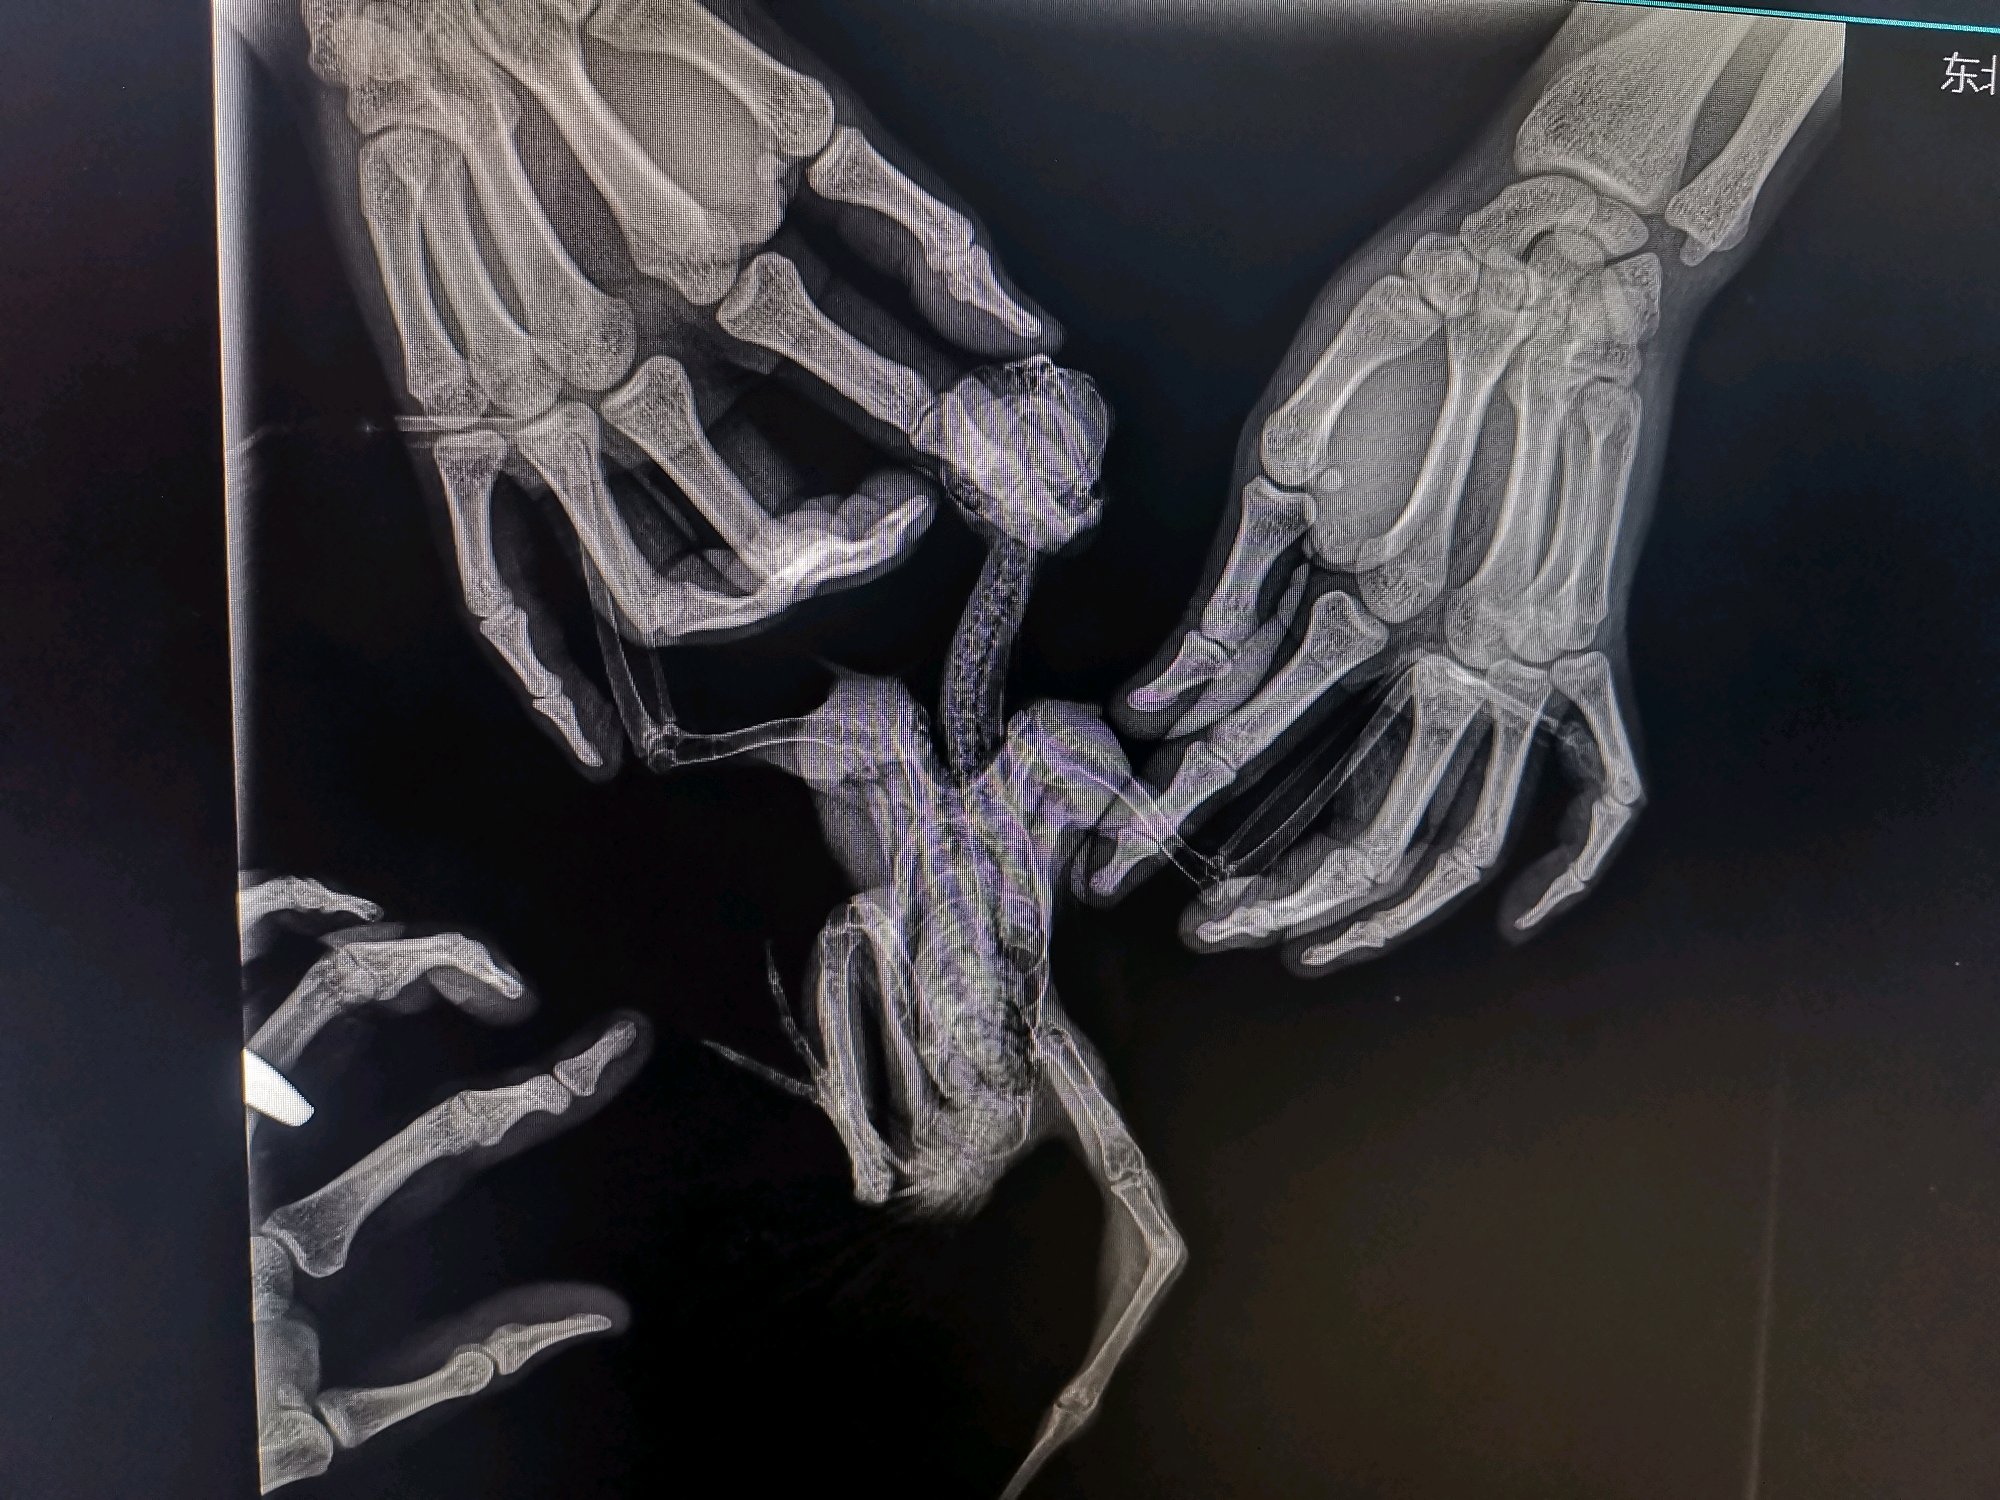

我是做通信的,因为基站拆迁,上面有鸟窝,等半天也没发现别的鸟来找他。他还小腿有点问题就救助他了。因为不懂,所以咨询了一个淘宝卖鹰具的一个人,他叫黑龙匠专业鹰隼用品,他说免费提供养护知识,还来看了我这红隼,我也是想治好他,那人说就是缺钙,我就给他喂钙片,确实好点了能站起来。但是也就到能站起来的程度了。我开始就怀疑不是缺钙,后来越来越这么觉得,我有点不相信他,问他好几次,他都说缺钙让我放心。后来我就到处找动物医院,拍片子显示那条腿有两处骨折,两个月了应该已经长好了,大夫说除非给腿两处敲折在接上,但是腿会短一块的不值得,鸟还要遭罪。说到这我真很怨这个淘宝商家,我都把鸟给你看了,要是早发现不至于这鸟一辈子都跛腿,一点没有责任心,都没仔细看,你要是仔细看,腿都鼓包了,我还好几次问你是不是腿有问题脱臼或者骨折。最后只能这样了,要求他赔偿或者别的也不可能,就是心疼这鸟。我也舍不得,但是总能看到这鸟在窗户向外望,他应该渴望自由。现在是没人干扰的情况下能站着,但是不稳。飞起来落地落到哪里,站不稳,扑腾一会才能站稳,有一条好腿,坏腿爪子能动,也有点力量。但是就是有点往外拐,大家可以看照片。请大家帮我看看,这还能放生嘛?我愿意养他一辈子,如果他开心自由我也可以放生,就怕他在外边活不了,不会打猎。请大家帮帮我。

以前腿折了,不知道。问一个淘宝卖鹰具的人他说是缺钙。让我喂钙片。鸟给他拿去了他都没好好看,给他发照片视频,他都没好好看。特别确定的告诉我就是缺钙,后来不信他去医院拍片子折了。那时候已经晚了。

我都去拍片子了。就是骨折了。我家红隼就是这么被人耽误的,误诊的。我要是不听早去拍片子就好了。